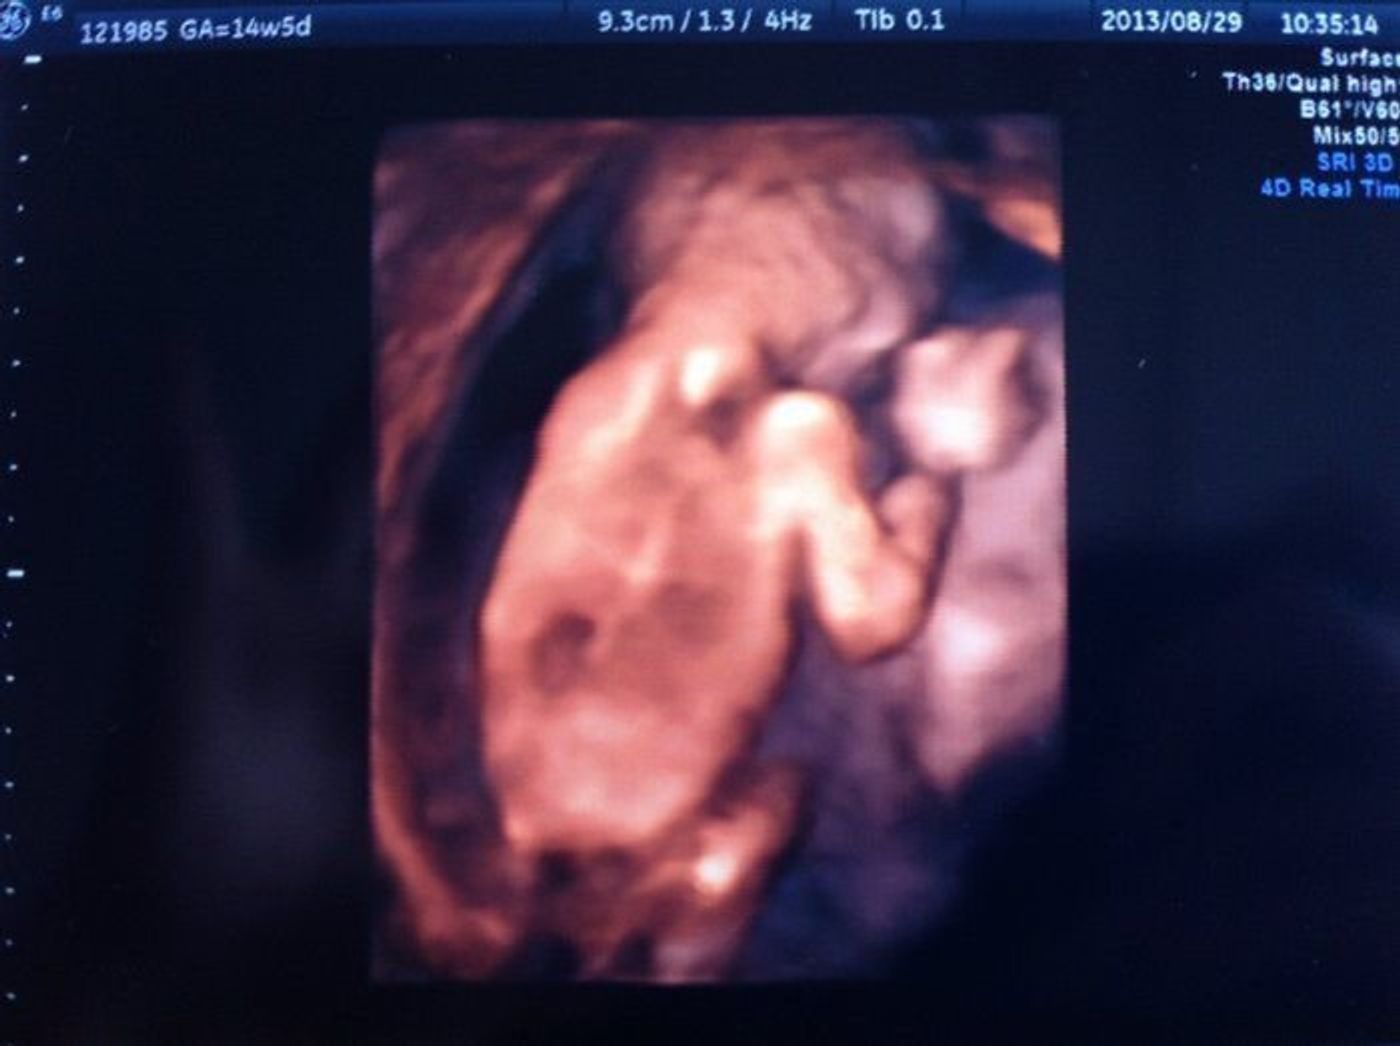

14週 エコー ダウン症-④ダウン症とわかるまで その4~緊急帝王切開による出産~ 実は 自宅の近所の産院では何も言われなかったのですが 14週の頃 里帰り先の病院で一度診てもらった際に指摘されたことがあります。 その時のエコーがこれです。 (苦手な方はご注意ください) エコー検査でbpdが長くても、flが短くても、ダウン症とは必ずしも結びつくことではない ようです。 妊娠初期の赤ちゃんの NT(首の後ろのむくみ) や、 内臓疾患 がないかどうか等、色々な要素から医師は異常の有無を判断しています。